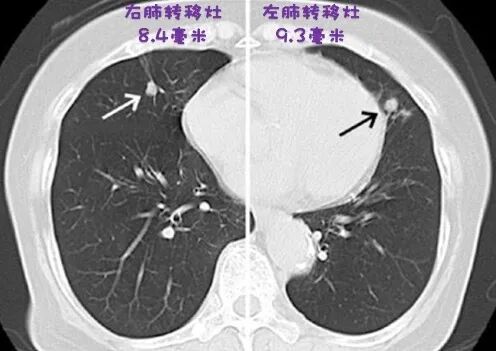

一直想通过案例的形式揭秘甲状腺癌 这样更容易帮助大家理解 但是缺乏长期完整的素材 最近有一本甲状腺新书出来了 中间有很多值得探讨的案例 这里和大家分享一下 治疗之路 今天的案例是70岁的日本女性 在日本Kuma医院就医 2001年因筛查颈动脉粥样硬化意外发现甲状腺癌 超声提示3.2厘米的甲状腺可疑结节 双侧四区均有可疑淋巴结 进一步检查提示气管受侵 当时的胸部CT无异常 手术切除了全部甲状腺和受侵的气管 同时清扫了双侧中央区侧颈区淋巴结 病理提示右侧乳头状癌,伴少量低分化成分 气管受侵,四枚淋巴结转移 2002年接受了100毫居的碘治疗 碘扫仅有残甲吸收 因为气管切缘阳性 同年接受了颈部外放疗 TSH一直抑制在0.1以内 之后的五年的随访没有异常 但抑制性Tg从2.8上升到11.4 最终2007年的胸部CT发现了端倪 左右肺分别有9.3和8.4毫米的转移灶 2008年接受了第二轮100毫居的碘治疗 可惜转移灶依旧没有摄取 只能继续观察 2012年右侧颈二区发现了可疑淋巴结 两枚淋巴结大小是11和9毫米 因为比较小并未进一步处理 2013年肺部转移灶增大到16.6和14.3毫米 2014年前的Tg增长还算稳定 自从2014年Tg来到58.8后 就有了爆发的趋势 2019年更是激增到1196 考虑到Tg增长的速度太快 2019年88岁的她接受了PET-CT的检查 结果提示骨转移 因为骨转移是单发的 所以Kuma医院准备使用外放疗控制骨转移 如果病情进一步发展就会考虑靶向治疗 甲癌的评估和揭秘 我希望通过这个案例 帮助大家了解甲状腺癌的复发风险分级,动态风险分层,生存率,以及发展规律 复发风险分级 术后两个月通过病理报告分级 复发风险分级(低危/中危/高危) 大面积腺外侵犯或淋巴结转移被分为高危 因为她的原发肿瘤侵犯气管 所以就是高危 这里高的其实是病灶残留的风险 很多人术后想知道有没有远处转移 如果被划分为低危或者中危 几乎没有远处转移的风险 但高危时一定会评估远处转移的可能 动态风险分层 术后两年通过治疗效果分层 动态风险分层(完美/不确定/生化异常/结构异常) 她2003年时并未出现明确复发 尽管抑制性Tg是3-4 所以Kuma医院划分她为生化异常 也就是Tg的数值不达标 但影像学上没有病灶 实际未必是生化异常 2007-2019年间她肺部转移灶的增速一致 每2.7年肺结节体积(非直径)增长一倍 2007年她肺部转移灶是9.3毫米 推算到确诊的2001年可能已经有5-6毫米 只不过那时仪器精度不大好 没被发现而已 大多数高危患者术后都是带癌生存 不是病灶已经出现在图像上 就是还在出现在图像的路上 大家最关心的就是生存率 如果复发风险分级是低危或中危的话 通常是没有死亡风险的 高危患者的生存率又如何估算呢? Tg倍增时间 10年生存率 <1年 90 60 1-3年 95 95 >3年 100 100 术后两个月的时候会评估肿瘤分期 按照最新的标准 她确诊时是T4aN1bM0,三期 初期评估的10年生存率是72.4% 后期评估则取决于Tg每长一倍需要的时间 她Tg的倍增时间是2.7年 对应的10年生存率是95% 事实也确实如此 18年后,88岁的她依然健在 但甲状腺癌也慢慢开始威胁她的生命 发展规律 这个案例也很好的体现了乳头状癌发展的基本规律 大多数乳头状癌是比较温柔的 一般只在颈部小范围活动 但当癌细胞比较凶时 比如有一些低分化成分 就可能在颈部大面积转移 接着病灶会在肺部生根发芽 当肺部转移到达一定程度 癌细胞才会跑到肺部以外的器官 治疗方案是否合理? 这是二十年前的案例 站在今天的角度看 她依然属于无法治愈的甲状腺癌 但她当时的治疗随访方案是否合理? 如果重头再来 有没有可以改进的地方?